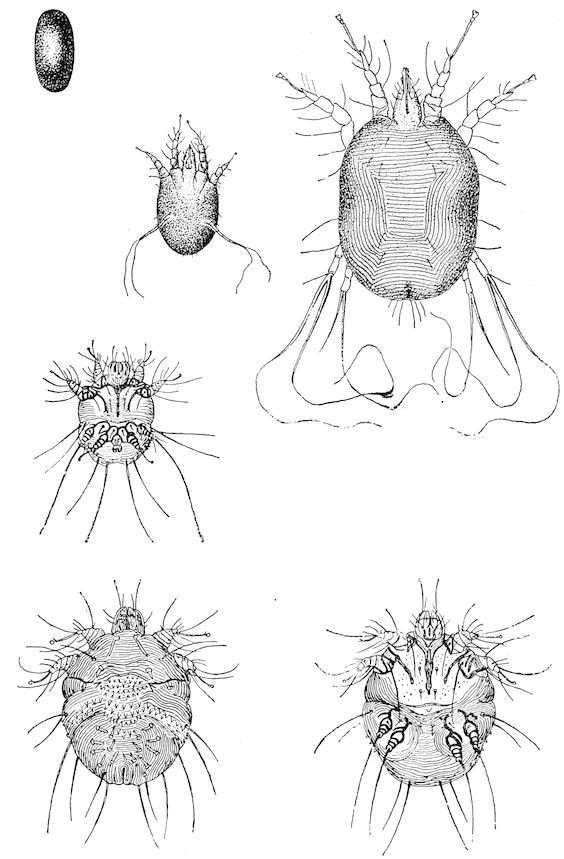

| Scabies—Scab—Mange | 611 | |||

| Scabies in sheep | 611 | |||

| Sarcoptic scabies | 612 | |||

| Psoroptic mange—Sheep scab | 614 | |||

| Chorioptic mange—Symbiotic mange—Foot scab | 636 | |||

| Demodecic mange | 643 | |||

| Demodecic mange in the ox | 644 | |||

| Demodecic mange in the goat | 644 | |||

| Demodecic mange in the pig | 644 | |||